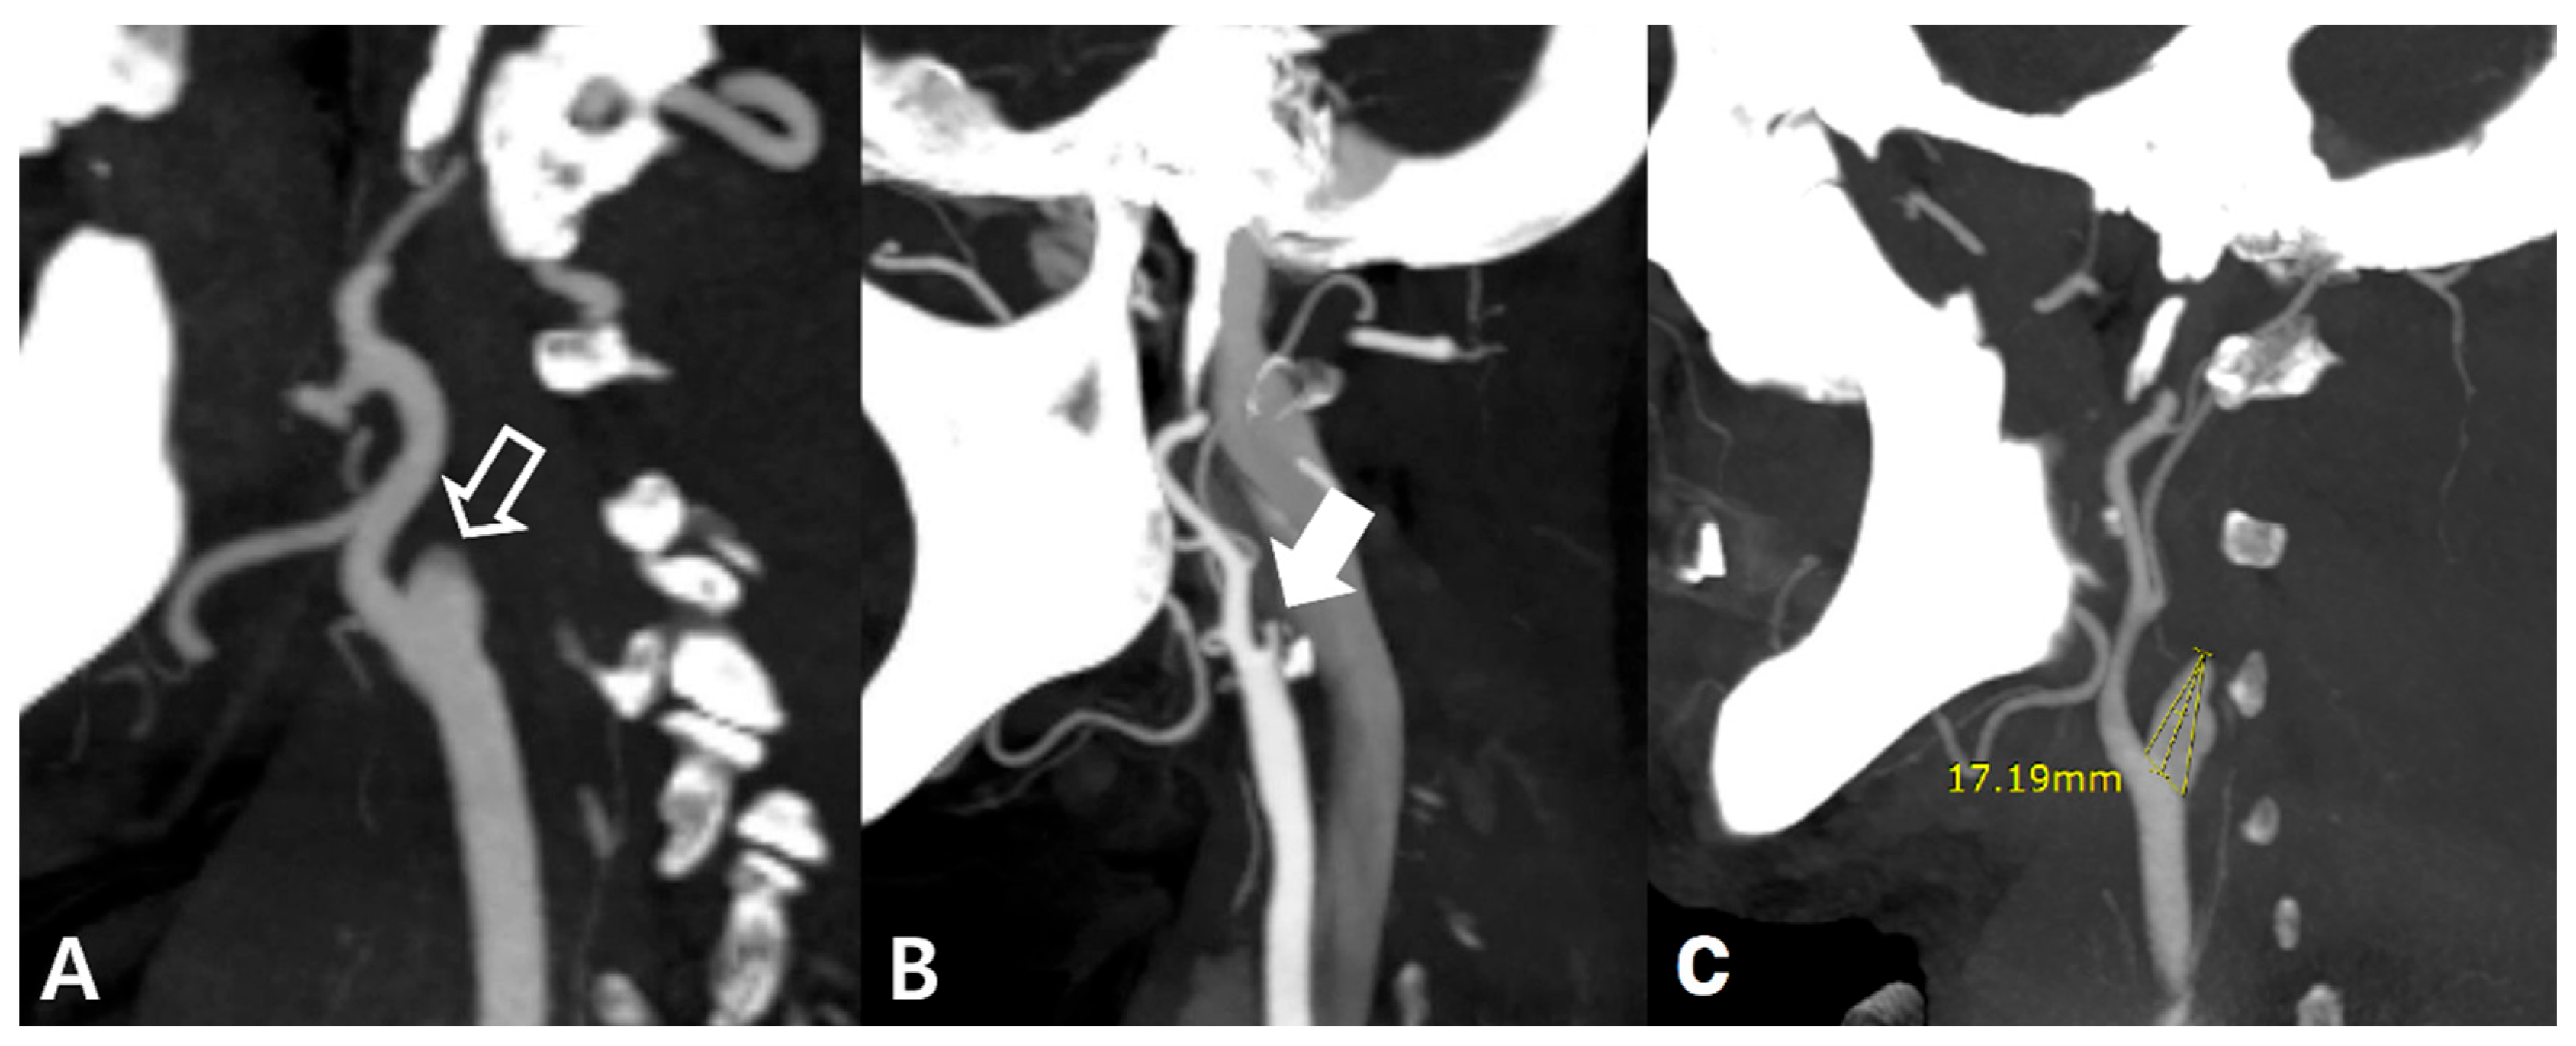

- Hong, J.M.; Lee, S.E.; Lee, S.J.; Lee, J.S.; Demchuk, A.M. Distinctive Patterns on CT Angiography Characterize Acute Internal Carotid Artery Occlusion Subtypes. Medicine 2017, 96, 5722. [Google Scholar] [CrossRef]

- Kim, H.; Kwak, H.S.; Chung, G.H.; Hwang, S.B. Differentiating Pseudo-Occlusion From True Occlusion of Proximal Internal Carotid Artery in Acute Ischemic Stroke on CT Angiography. Clin. Neurol. Neurosurg. 2019, 185, 105495. [Google Scholar] [CrossRef]